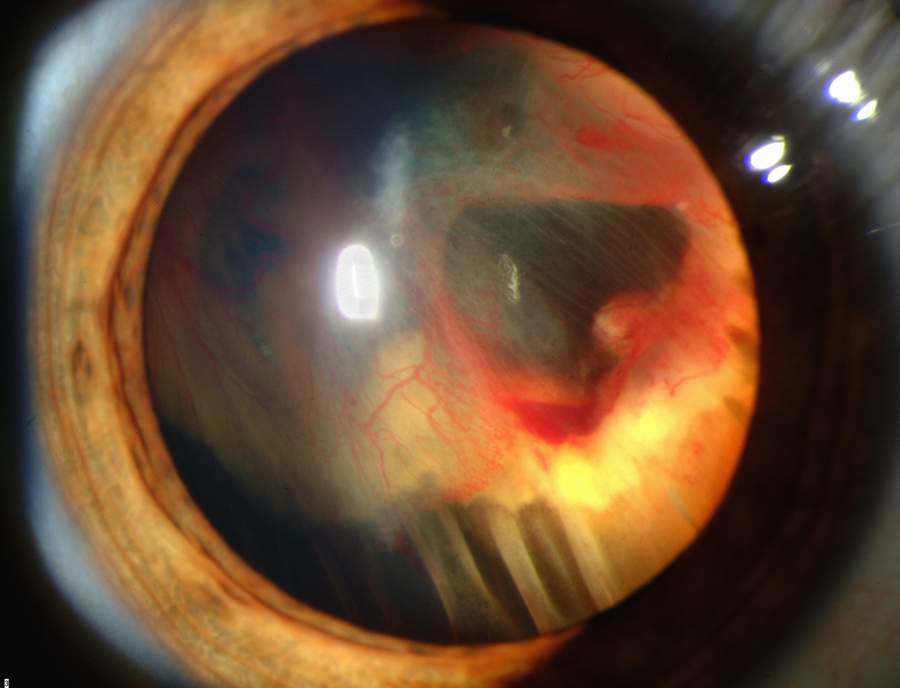

Warning Signs of Retinal Detachment

Learn the symptoms that require urgent care and how early treatment protects vision.